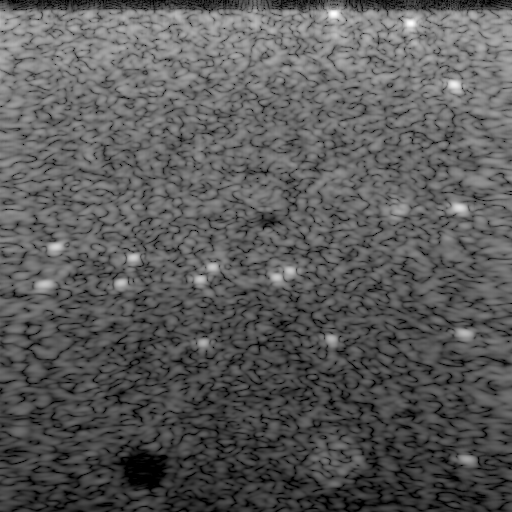

2.11.1F-number (1) 4.56.1Frequency f𝑓f (MHz) Refer to caption5.7 mm/times5.7dividemillimeterabsent5.7\text{\,}\mathrm{mm}\text{/} 1 mm/times1dividemillimeterabsent1\text{\,}\mathrm{mm}\text{/} (a)Refer to caption5.3 mm/times5.3dividemillimeterabsent5.3\text{\,}\mathrm{mm}\text{/} 0.8 mm/times0.8dividemillimeterabsent0.8\text{\,}\mathrm{mm}\text{/} (b)25 dB/times-25dividedecibelabsent-25\text{\,}\mathrm{dB}\text{/} Refer to caption3.1 mm/times3.1dividemillimeterabsent3.1\text{\,}\mathrm{mm}\text{/} 0.5 mm/times0.5dividemillimeterabsent0.5\text{\,}\mathrm{mm}\text{/} Axial position z𝑧z(c)-404040 -303030 -202020 -101010 00 dB/dividedecibelabsent\mathrm{dB}\text{/}29 dB/times-29dividedecibelabsent-29\text{\,}\mathrm{dB}\text{/} Lateral position x𝑥xRefer to caption2.4 mm/times2.4dividemillimeterabsent2.4\text{\,}\mathrm{mm}\text{/} 0.5 mm/times0.5dividemillimeterabsent0.5\text{\,}\mathrm{mm}\text{/} (d)18 dB/times-18dividedecibelabsent-18\text{\,}\mathrm{dB}\text{/} Lateral FWHMDOFGLL

Figure 1: Effects of the F-number (1) and the frequency f𝑓f on the focused beam. A decrease in the F-number (1) or an increase in the frequency f𝑓f has the following effects: 1) the lateral FWHM and the DOF decrease; and 2) the GLL increases. Frequency dependence of the F-number (1), hence, can keep constant a selected metric, such as the DOF or the GLL. The images show the focused beam at the center frequency (left column) and near the upper frequency bound (right column) with the lateral and axial profiles for a large F-number (top row) and a small F-number (bottom row). The axes in all images are equal.

The F-number (1) and the frequency f𝑓f, as shown in Fig. 1, determine essential properties of the focused beam. These properties include: 1) the lateral full width at half maximum (FWHM); 2) the DOF; and 3) the grating lobe level (GLL). As the F-number (1) decreases or the frequency f𝑓f increases, the lateral FWHM and the DOF decrease. Both properties indicate ranges of positions over which the beam is focused satisfactorily. The lateral FWHM equals the distance between the lateral positions in the focal plane where the beam intensity reduces by 6 dB/times6dividedecibelabsent6\text{\,}\mathrm{dB}\text{/} [7, p. 173]. Smaller lateral FWHM indicate better lateral resolution. The DOF, similarly, equals the distance between the axial positions where the beam intensity reduces by 2.2 dB/times2.2dividedecibelabsent2.2\text{\,}\mathrm{dB}\text{/} [7, p. 173], [10, p. 491]. This property, owing to the few transmit focal lengths zfsubscript𝑧fz_{\text{f}} in a compound image (see Sect. I), is only relevant to the transmit focusing. Larger DOFs reduce image degradation away from the transmit focal length zfsubscript𝑧fz_{\text{f}}. The GLL, in contrast, increases as the F-number (1) decreases or the frequency f𝑓f increases. The GLL denotes the ratio of the maximum amplitudes attained by the grating lobes and the main lobe [3, 6] and indicates the dynamic range available for unambiguous imaging. Smaller GLLs reduce grating lobe artifacts.